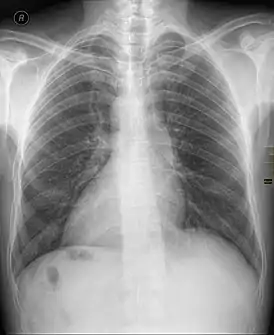

![]() Декстрокардия в рамках situs inversus на рентгенограмме органов грудной клетки. | |